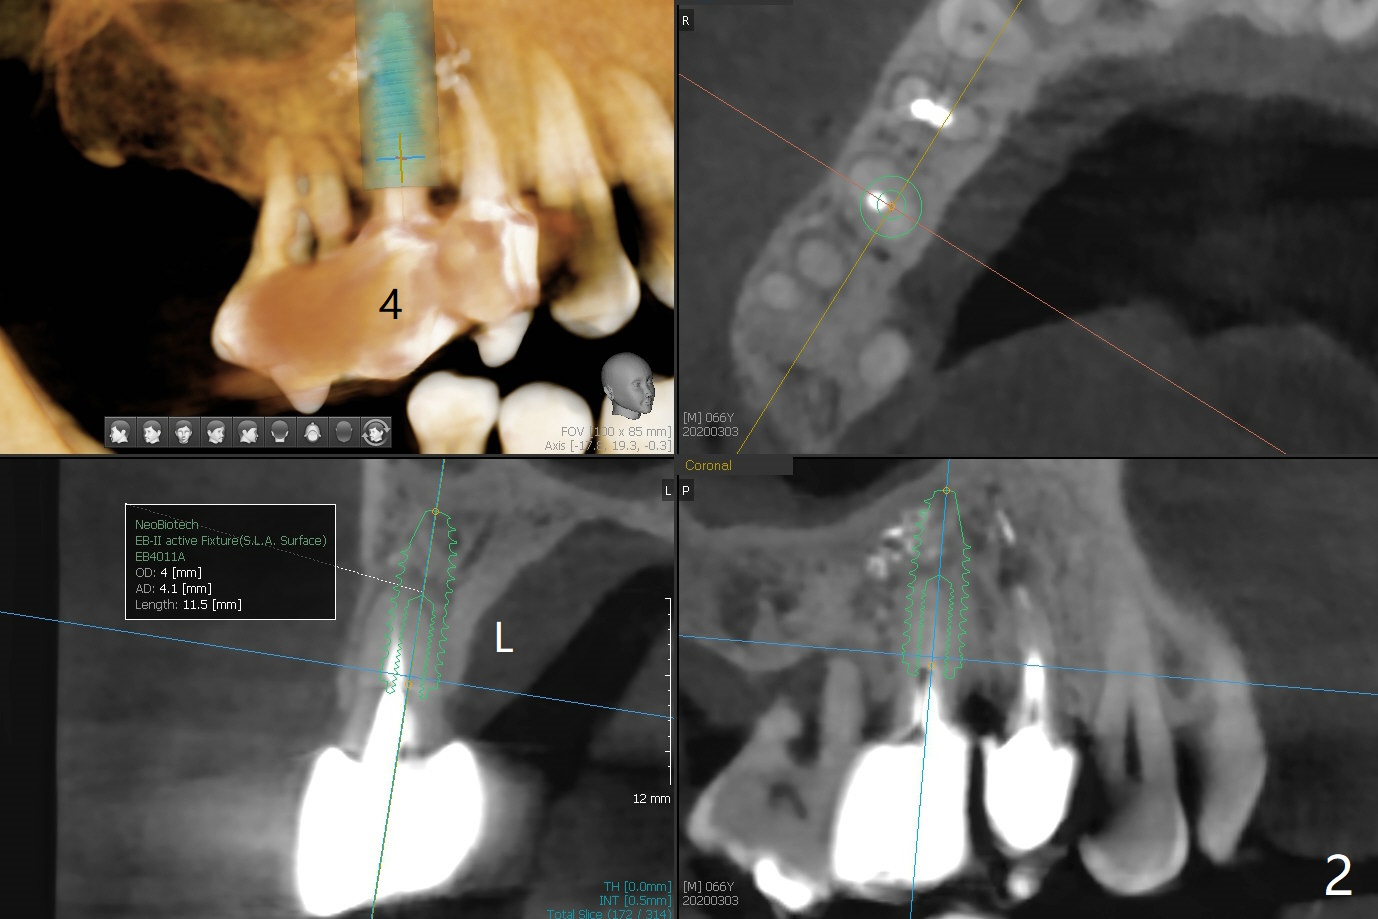

A 66-year-old man has lower RPD. Masti-cation is difficult due to #4 root fracture and #13 and 14 missing (Fig.1). After extraction of #4 with socket antibiotic treatment (Fig.2), finish #13 and 14 osteotomy and implant placement (Fig.3,4). Save auto-genous bone from #13, 14 and #4 using suction trap for #4 buccal gap closure.